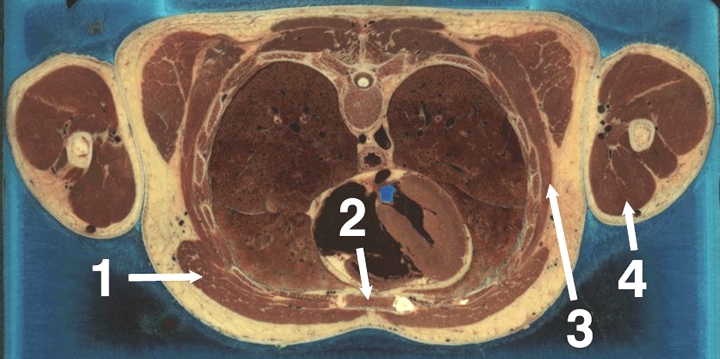

General Upper Body Reconstructions